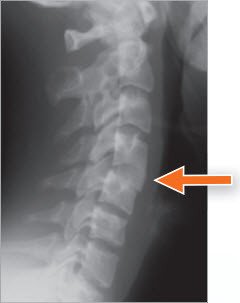

Die Bandscheiben sind flüssigkeitshaltige Kissen aus zähem und elastischem Bindegewebe. Sie verbinden je zwei Wirbelkörper miteinander und ermöglichen die Bewegung der Wirbelsäule. Eine besondere Form des Bandscheibenverschleisses ist die Diskushernie (Bandscheibenvorfall). Wenn die Bandscheibe nicht mehr ausreichend widerstandsfähig ist, wölbt sich ihre Fläche, und es kommt zu einer Bandscheibenprotrusion (Vorwölbung), oder ein Stück der Bandscheibe löst sich von der Bandscheibenmasse und drängt sich aus dem Raum zwischen den Wirbelkörpern in den Nervenkanal heraus (Bandscheiben-Hernie).

Der Vorfall einer Bandscheibe an der Halswirbelsäule kann eine der Nervenwurzeln einklemmen, die Arm und Hand versorgen. Der Patient hat oft Schmerzen im Genick, die stärker werden, wenn er den Kopf bewegt, sowie Schmerzen, Gefühlsstörungen und Schwäche in einem Arm und in einer Hand. Schwäche und Gefühlsstörungen können besonders in der Gebrauchshand behindernd sein. Nur selten kann ein grosser Bandscheibenvorfall dazu führen, dass das Rückenmark eingeklemmt wird, was Steifigkeit der Beine verursachen und dadurch zu Gehschwierigkeiten führen kann.

Manchmal wird zusätzlich zur Nervenwurzel das Rückenmark eingeengt, was zu Lähmungssymptomen auch in den Beinen führen kann. Dringlich durchgeführt wird eine Operation bei schwerer Einklemmung des Rückenmarks oder einer Nervenwurzel. Bei kleineren Vorfällen wird mit konservativer Behandlung, die in der Regel bis zu sechs Wochen dauert, eine Besserung angestrebt.

Die Vorderfläche der Halswirbelsäule wird durch einen kleinen Hautschnitt entlang einer Hautfurche auf der rechten Seite des Halses freigelegt. Dieses Verfahren wird auch bei Beschwerden des linken Armes eingesetzt. Der Bandscheibenvorfall (Hernie), welcher die Nervenwurzel reizt und einklemmt, wird mit dem Mikroskop identifiziert und entfernt. In ausgewählten Fällen kann die Hernie (Bandscheibenvorfall) nur von hinten entfernt werden.